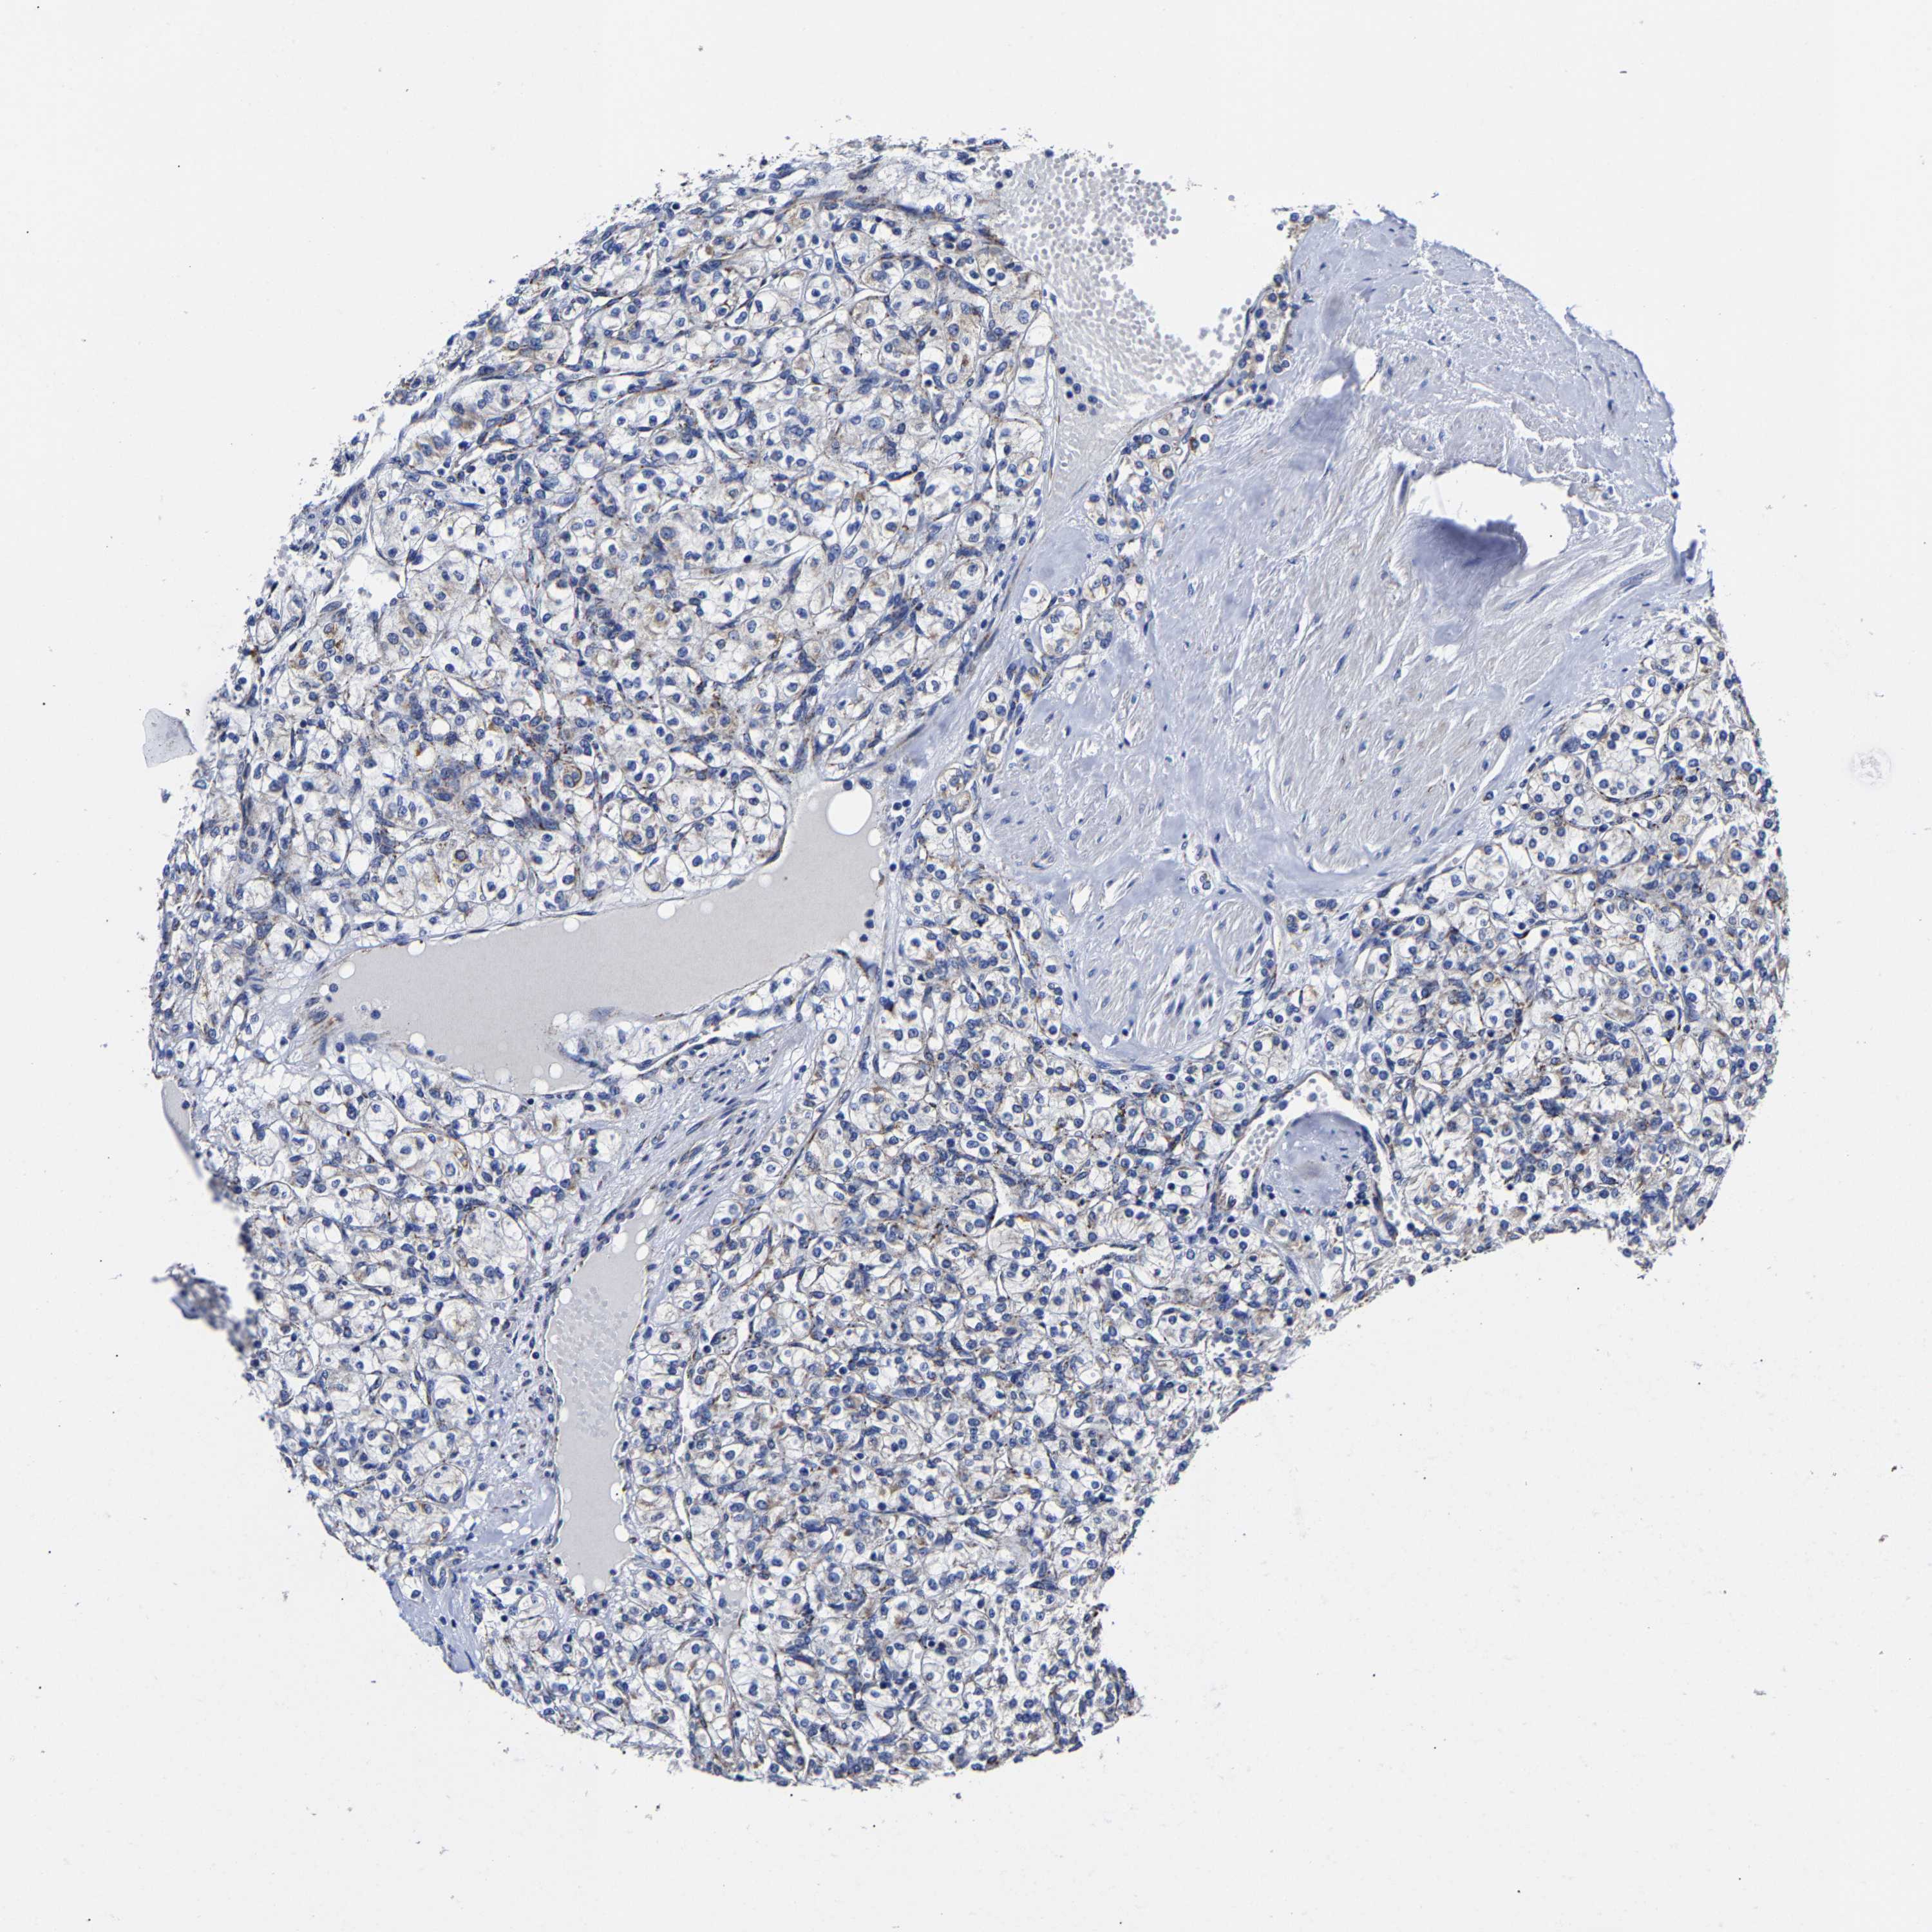

KIDNEY RENAL CLEAR CELL CARCINOMA (TCGA) - Interactive survival scatter ploti

The Survival Scatter plot shows the clinical status (i.e. dead or alive) for all individuals in the patient cohort, based on the same data that underlies the corresponding Kaplan-Meier plots. Patients that are alive at last time for follow-up are shown in blue and patients who have died during the study are shown in red.

The x-axis shows the expression levels (FPKM) of the investigated gene in the tumor tissue at the time of diagnosis. The y-axis shows the follow-up time after diagnosis (years). Both axes are complimented with kernel density curves demonstrating the data density over the axes. The top density plot shows the expression levels (FPKM) distribution among dead (red) and alive patients (blue). The right density plot shows the data density of the survived years of dead patients with high and low expression levels respectively, stratified using the cutoff indicated by the vertical dashed line through the Survival Scatter plot. This cutoff is automatically defined based on the FPKM cutoff that minimizes the p-score. The cutoff can be changed by dragging the vertical line or by entering a cutoff value in the square labeled "Current cut-off".

Under the Survival Scatter plot the p-score landscape (black curve; left axis) is shown together with dead median separation (red curve; right axis). Dead median separation is the difference in median mRNA expression between patients who have died with high and low expression, respectively. It is calculated as follows: median FPKM expression of dead patients with high expression - median FPKM expression of dead patients with low expression. This is intended to aid the user in visually exploring custom cutoffs and the associated p-scores and dead median separation.

Individual patient data is displayed and can be filtered by clicking on one or more of the category buttons on the top of the page. Categories describing expression level and patient information include: high, low, alive, dead, female, male and tumor stages. The scale of the x-axis can be toggled between linear and log-scale by clicking on the "x log" button. Mouse-over function shows TCGA ID, patient information and mRNA expression (FPKM) for each patient.

& Survival analysisi

Kaplan-Meier plots summarize results from analysis of correlation between mRNA expression level and patient survival. Patients were divided based on level of expression into one of the two groups "low" (under cut off) or "high" (over cut off). X-axis shows time for survival (years) and y-axis shows the probability of survival, where 1.0 corresponds to 100 percent.

AASS is not prognostic in Kidney Renal Clear Cell Carcinoma (TCGA)

Best expression cut offi

Based on the FPKM value of each gene, patients were classified into two groups and association between prognosis (survival) and gene expression (FPKM) was examined. The best expression cut-off refers the FPKM value that yields maximal difference with regard to survival between the two groups at the lowest log-rank P-value. Best expression cut-off was selected based on survival analysis .

When clicking on this number, the vertical dashed line indicating cut-off, the interactive survival plot, and the Kaplan-Meier curve will be adjusted to show results based on the best expression cut-off.

: 2.95

TCGA RNA samplesi

RNA-seq data is reported as average FPKM (number Fragments Per Kilobase of exon per Million reads), generated by the The Cancer Genome Atlas (TCGA) .

Normal distribution across the dataset is visualized with box plots, shown as median and 25th and 75th percentiles. Points are displayed as outliers if they are above or below 1.5 times the interquartile range. FPKM values of the individual samples are presented next to the box plot.

Average pTPM 3.6

Number of samples 521